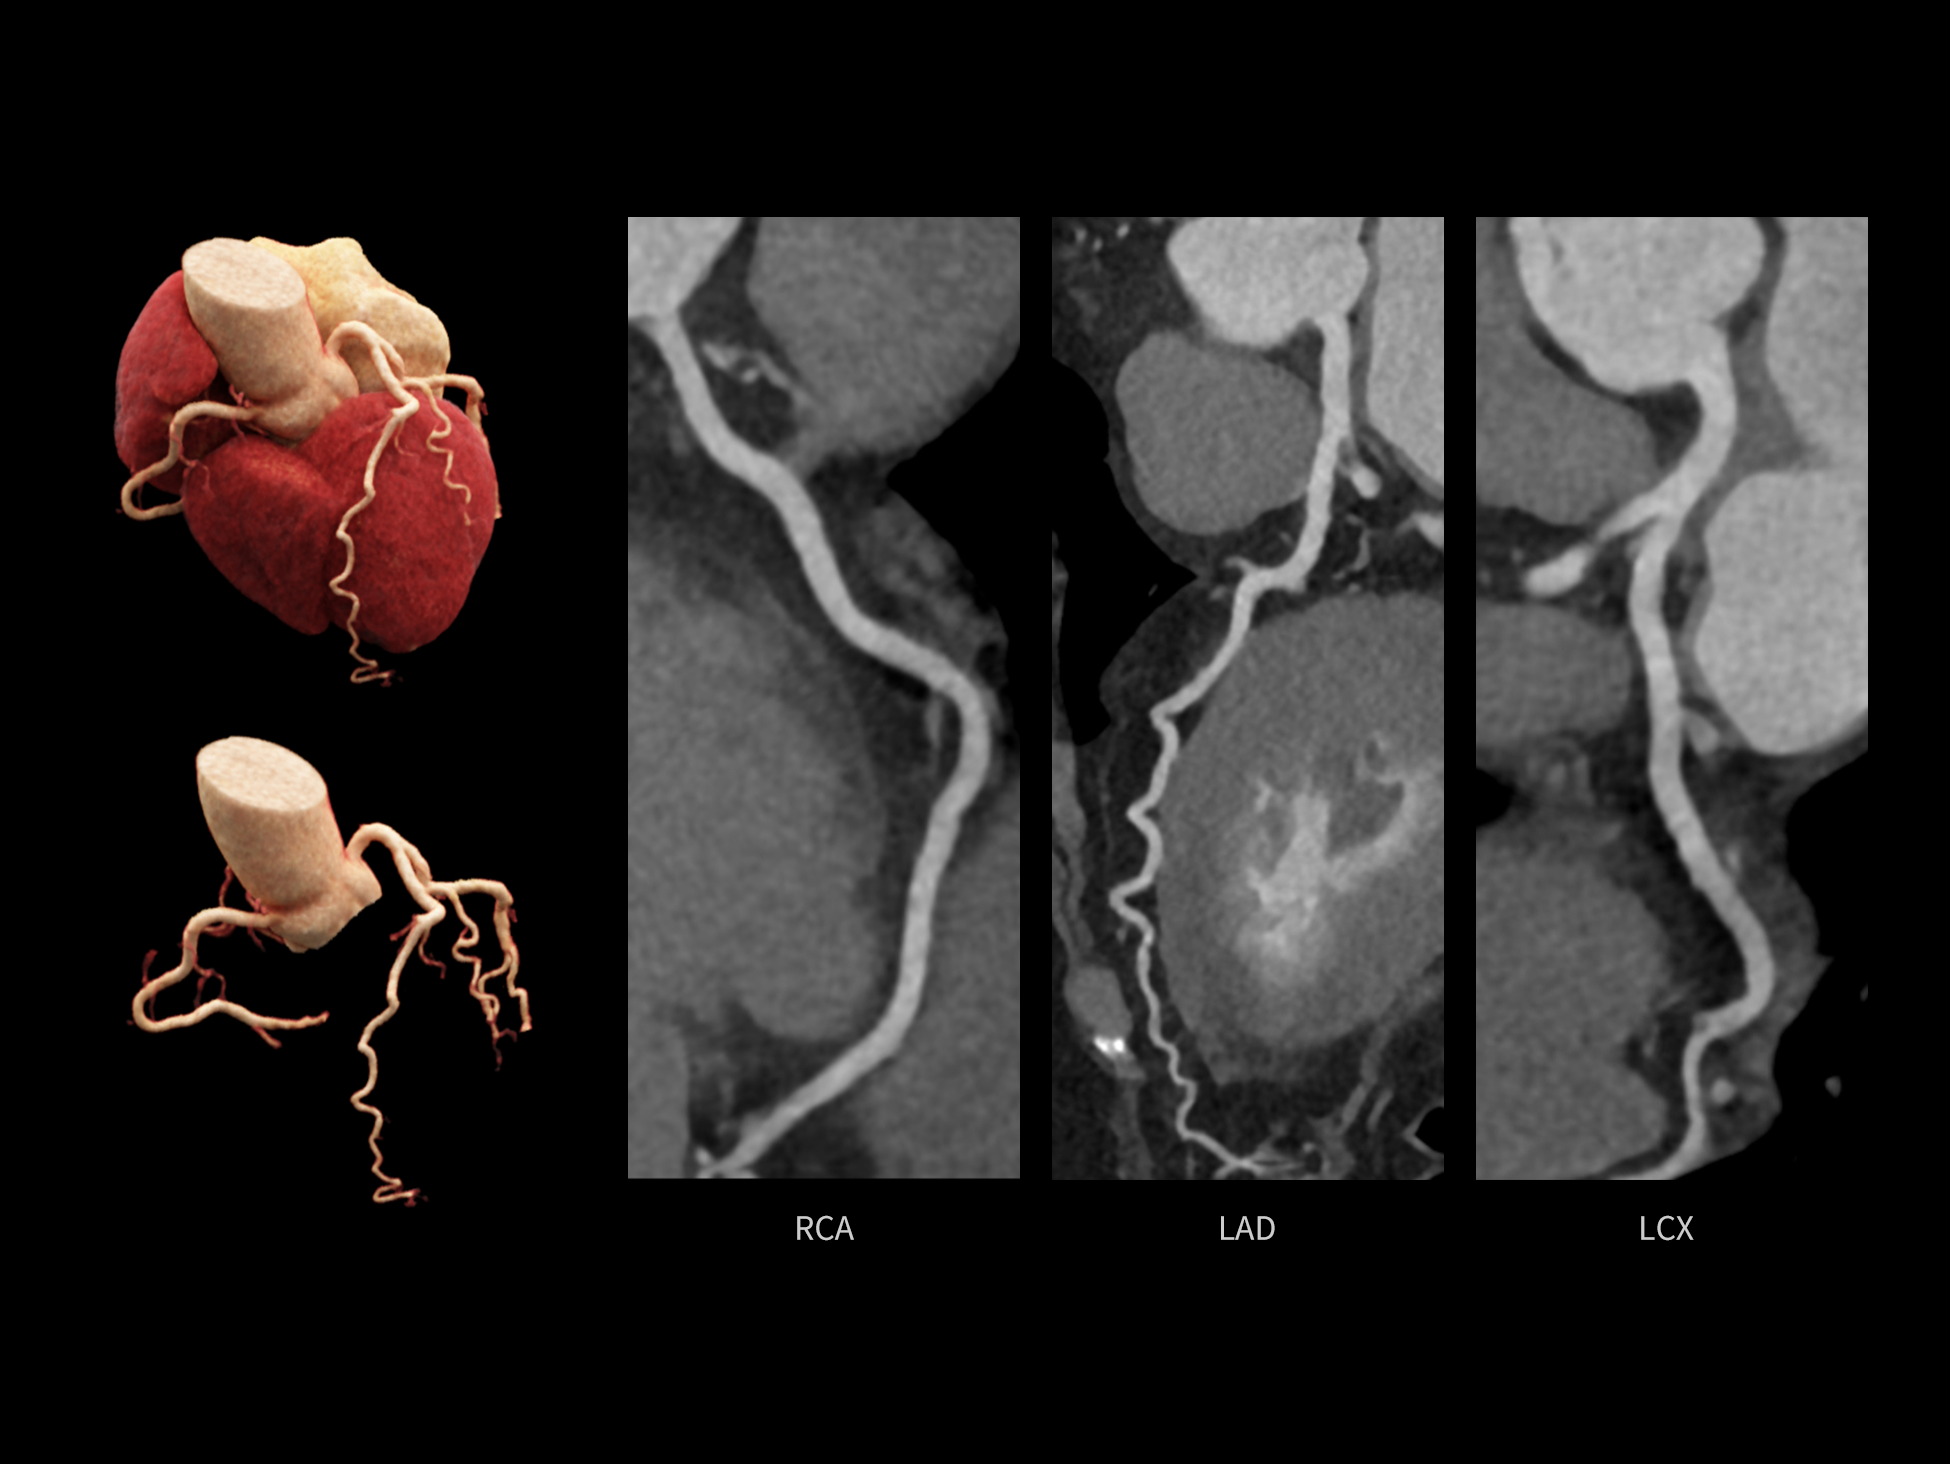

CardioCapture 2.0 通过“识别–追踪–建模–校正”的完整流程,精准分割心脏结构,动态追踪运动轨迹,并构建多时相运动场,最终实现冠脉、瓣膜、心肌及心室结构的同步校正,清晰洞见每一次心跳细微变化,真正将心脏动态掌握于毫秒之间。

CardioCapture 2.0 在目标时相前后重建多时相影像,通过深度学习网络精准提取冠脉中心线,进而建立时相间运动模型,实现对冠脉分段图像的精准运动校正。

冠脉运动校正

全心结构运动校正

CardioCapture 2.0 可对心肌、瓣膜及心室等结构进行同步运动校正。基于深度学习的心脏精细分割,实现了更完整的心脏全局信息提取,能有效抑制全心运动伪影,显著提升心脏细节的清晰度与诊断可靠性。

全心全时相高清成像

单心动周期内的任意时相获取高质量的冠脉CTA图像,确保稳定的心脏成像效果。